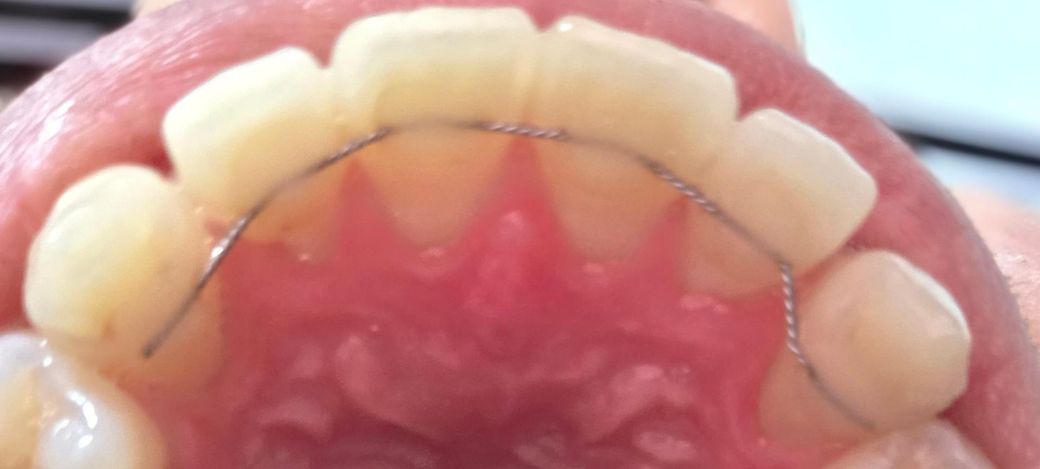

고정식 치아 교정장치 형태정상인가요?

오른쪽이 왼쪽이랑은 철사가 휘어진것처럼 다른데 시간이 오래되면서 변형이 된건지 아니면 원래부터 치아에 맞게 차이가 있었던건지 모르겠네요

고정식 교정장치의 경우에는 움직이거나 변형되지 않는것이 정상입니다. 유지장치가 변형이 되었다면 해당부위에 힘이 작용하거나 치아를 정상적으로 유지해 주지 못할수 있습니다.

이런경우 유지장치를 새로 제작해야 할수 있습니다.

고정식 유지장치가 원래 그렇게 부착되어 있었을 것으로 예상됩니다. 특별히 문제는 안보입니다.

사진상으로 보면 유지장치에는 문제가 없는거 같습니다. 변형이 된건 없으니 너무 걱정하지마세요.

현재 사진만으로는 정확한 판단이 어렵습니다. 말씀하신 FR(Fixed retainer)의 경우에는 환자의 치아 모양에 맞게 제작하게 됩니다. 만약 해당 철사가 갑자기 구부려지거나 맞지 않다면 치아에 힘이 가해져 치통이 발생할 수 있습니다. 단순 사진으로 모양이 변한 것 이외에 통증이나 불편감이 있는지 우선 체크해야 합니다. 그렇지 않다면 현재 사진으로 봐서는 크게 문제가 되는 부위는 보이지 않습니다.

설측교정 중 입니다. 철사 방향이나 각도는 치아의 위치에 따라 조금씩 다르게 나옵니다. 사진에서 보이는 것 정상적인 것입니다.

치아 표현 모양에 맞춰 굴곡이 있는 것으로 보입니다 사진상으로 봤을때 장치에 문제는 없어보입니다